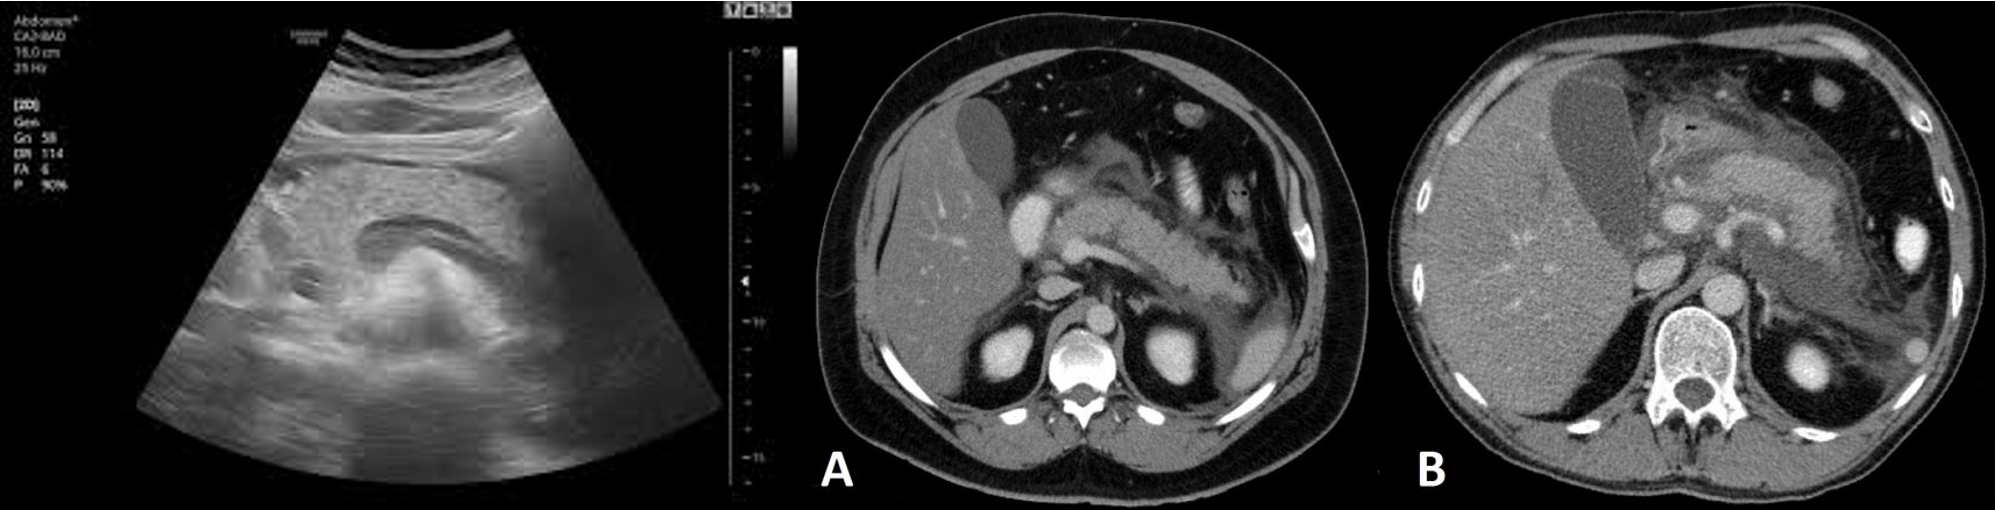

• Imaging:

• Ultrasound abdomen: gallstone.

• Abdominal CT: diagnosis, complications of acute pancreatitis, evidence of necrotizing pancreatitis.

CT abdomen Pancreatitis

• Although a CT scan may eventually be useful, it will not be as helpful as the other choices at this point. It is best used at 72 hours of illness to assess the degree of pancreatic necrosis in patients with predicted severe disease.